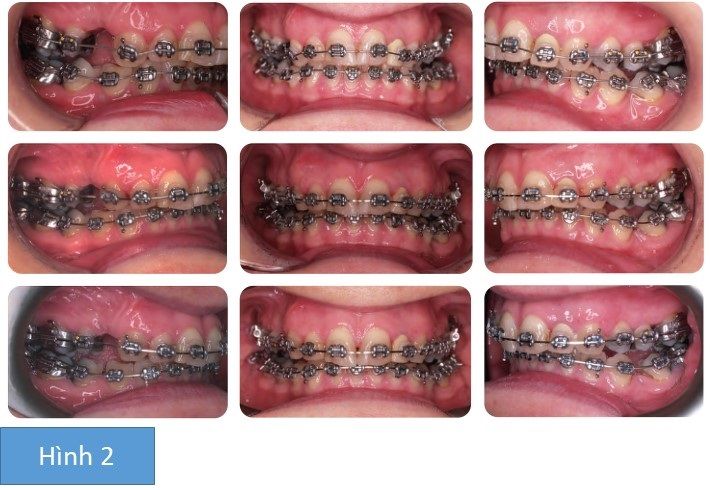

Điều gì đã xảy ra với R22?

Mắc cài được gắn lên mão sứ, bị bog ra và thất lạc trước phẫu thuật! Thay vì gắn nó lại, bác sĩ quyết định để mặc nó tới sau khi phẫu thuật xong và thay thế nó trước khi tinh chỉnh khớp cắn cuối cùng.